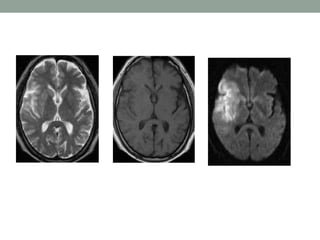

Fluid-attenuated inversion recovery

(FLAIR)

• T2-weighted imaging is well suited for lesion detection in

the brain because most lesions appear hyperintense with

this sequence.

• However CSF also appears hyperintense on T2-weighted

spin-echo (SE) images.

• Therefore, lesions at CSF interfaces, such as cortical sulci

and ventricles, may be mistaken for extensions of CSF or

partial volume effects.

• FLAIR imaging suppresses signal from free water in CSF

and maintains hyperintense lesion contrast.

• FLAIR sequences are particularly useful in evaluation of

MS, infarcts, SAH

Which scan best defines the

abnormality

T1 W Images:

Subacute Hemorrhage

Fat-containing structures

Anatomical Details

T2 W Images:

Edema

Demyelination

Infarction

Chronic Hemorrhage

FLAIR Images:

Edema,

Infarction esp. in Periventricular location